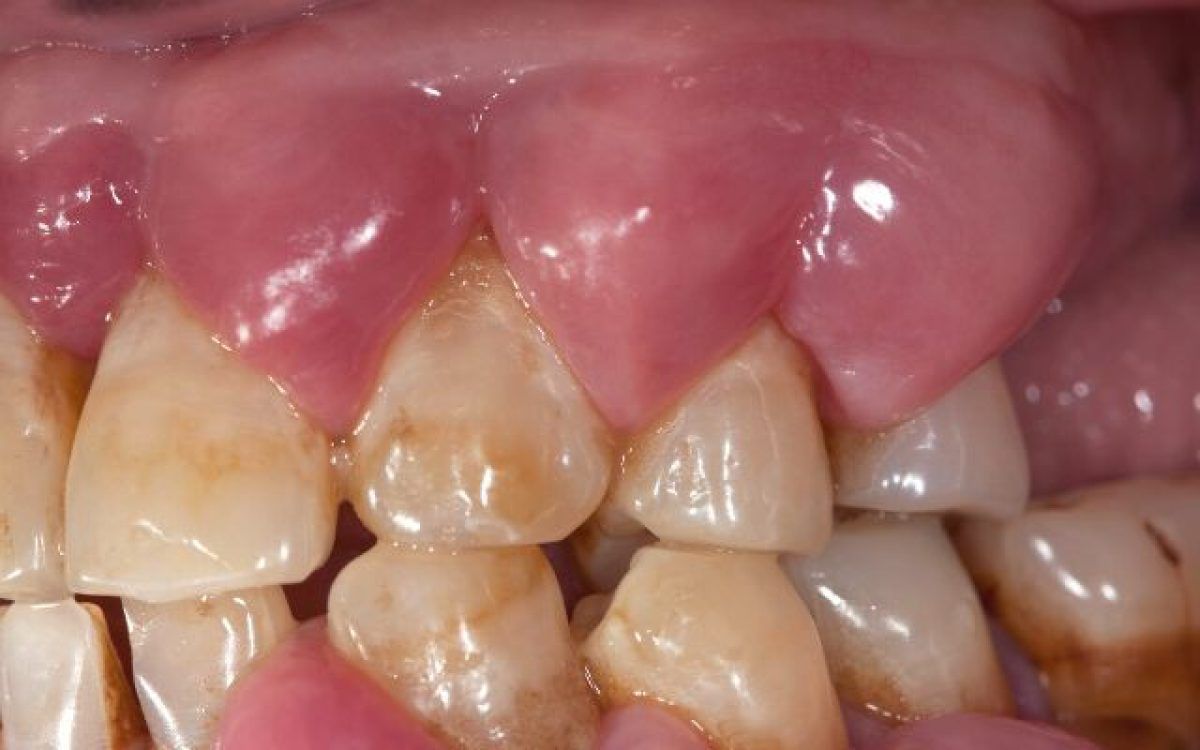

A periodontal abscess forms when bacteria from your mouth invade the space between your teeth and gums. Gum disease is the most common reason why this occurs, and it’s the number one risk factor for periodontal abscesses. You’re also more likely to develop a gum abscess if you have: Bruxism (chronic teeth grinding and clenching). Teeth damaged by injury or trauma. Broken or damaged restorations such as dental fillings, crowns or bridges.